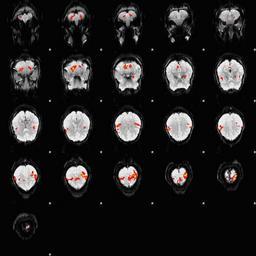

MAKE A MEME View Large Image Fingertapping experiment DXIII.jpg en An fMRI depiction of activated brain areas BOLD during an index finger-tapping sequence Experiment and imaging was performed in our dept at RIC at UTHSCSA Analysis for activation depiction was performed ...

Keywords: Fingertapping experiment DXIII.jpg en An fMRI depiction of activated brain areas BOLD during an index finger-tapping sequence Experiment and imaging was performed in our dept at RIC at UTHSCSA Analysis for activation depiction was performed by me using fsl I used BET FAST and FEAT to obtain this image The experiment was performed in the following method Subjects performed a finger tapping sequence during a block design paradigm This study focused on only right hand unimanual index finger During the first 30 seconds the subjects moved their right index finger from side to side adduction-abduction at the rate of 2Hz followed by a 30 second rest period This sequence was repeated 6 times for a total of 6 minutes A Gradient-Echo planar sequence was used with the parameters of TR 2s TE 30ms and a flip angle of 90° and sixteen continuous 6mm-thick axial slices with an in-plane spatial resolution of 3mmX3mm I derived Own Zereshk This image was not published anywhere and was part of my class project Functional magnetic resonance imaging Sequence